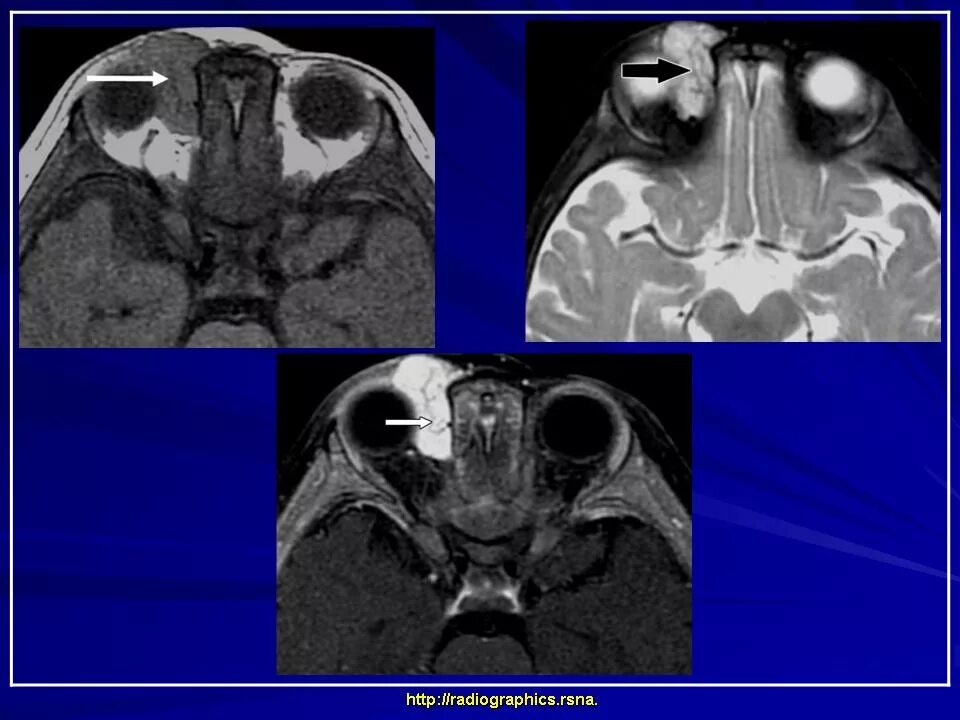

Данные кт